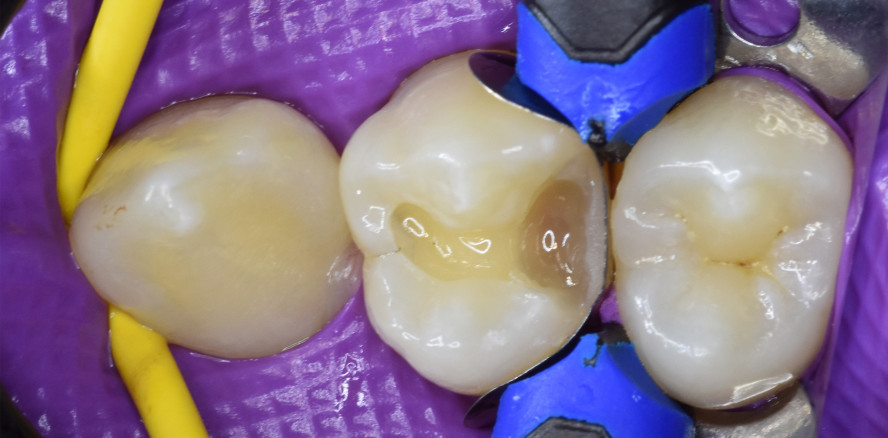

Im vorliegenden Fall wurde zunächst ein Kofferdam gelegt und die Karies ex kaviert (Abb. 3). Abbildung 4 zeigt die Situation nach abgeschlossener Ka vi tätenpräparation. Dann wurde ein Matrizenband (Composi-Tight Gold®, Garrison) mittels Matrizenring (Composi-Tight® 3D XR Ring, Garrison) sowie Holzkeilen in Position gebracht (Abb. 5). Die goldenen Matrizenbänder sind besonders dünn und ermöglichen so eine optimale Approximalpunktgestaltung. Es folgten die selektive Schmelzätzung mit 35-prozentigem Phosphorsäuregel für 15 Sekunden sowie anschließend die Applikation eines Universaladhäsivs (3M Scotchbond Universal Adhäsiv) (Abb. 6 und 7). Das Adhäsiv wurde gemäß der Gebrauchsanweisung für 20 Sekunden in die Zahnhartsubstanz einmassiert, danach bis zur vollständigen Evaporation des Lösungsmittels mit Luft verblasen und schließlich polymerisiert.

Nun wurde der approximale Kasten in einer Schicht mit Filtek One (Farbe A2) aufgebaut und der entstandene Hohlraum mit dem fließfähigen Komposit aufgefüllt (Abb. 8 und 9). Nach der Entfernung des Matrizenbandes wurde dann die finale Schicht aus hochviskosem Filtek One Komposit appliziert (Abb. 10). Für die Modellation der Okklusalfläche kamen LiquidSteel PolyFill Plasma+ Füllungsinstrumente (u.a. feiner spitzer Kegel, abgerundeter Kegel und Füllspatel, Carl Martin) zum Einsatz (Abb. 11).

Abbildung 12 zeigt die Situation vor der groben Ausarbeitung mit Hartmetallfinierern für die Füllungsbearbeitung (Komet Dental), Abbildung 13 die Situation nach diesem Vorgang sowie der Okklusionskontrolle.